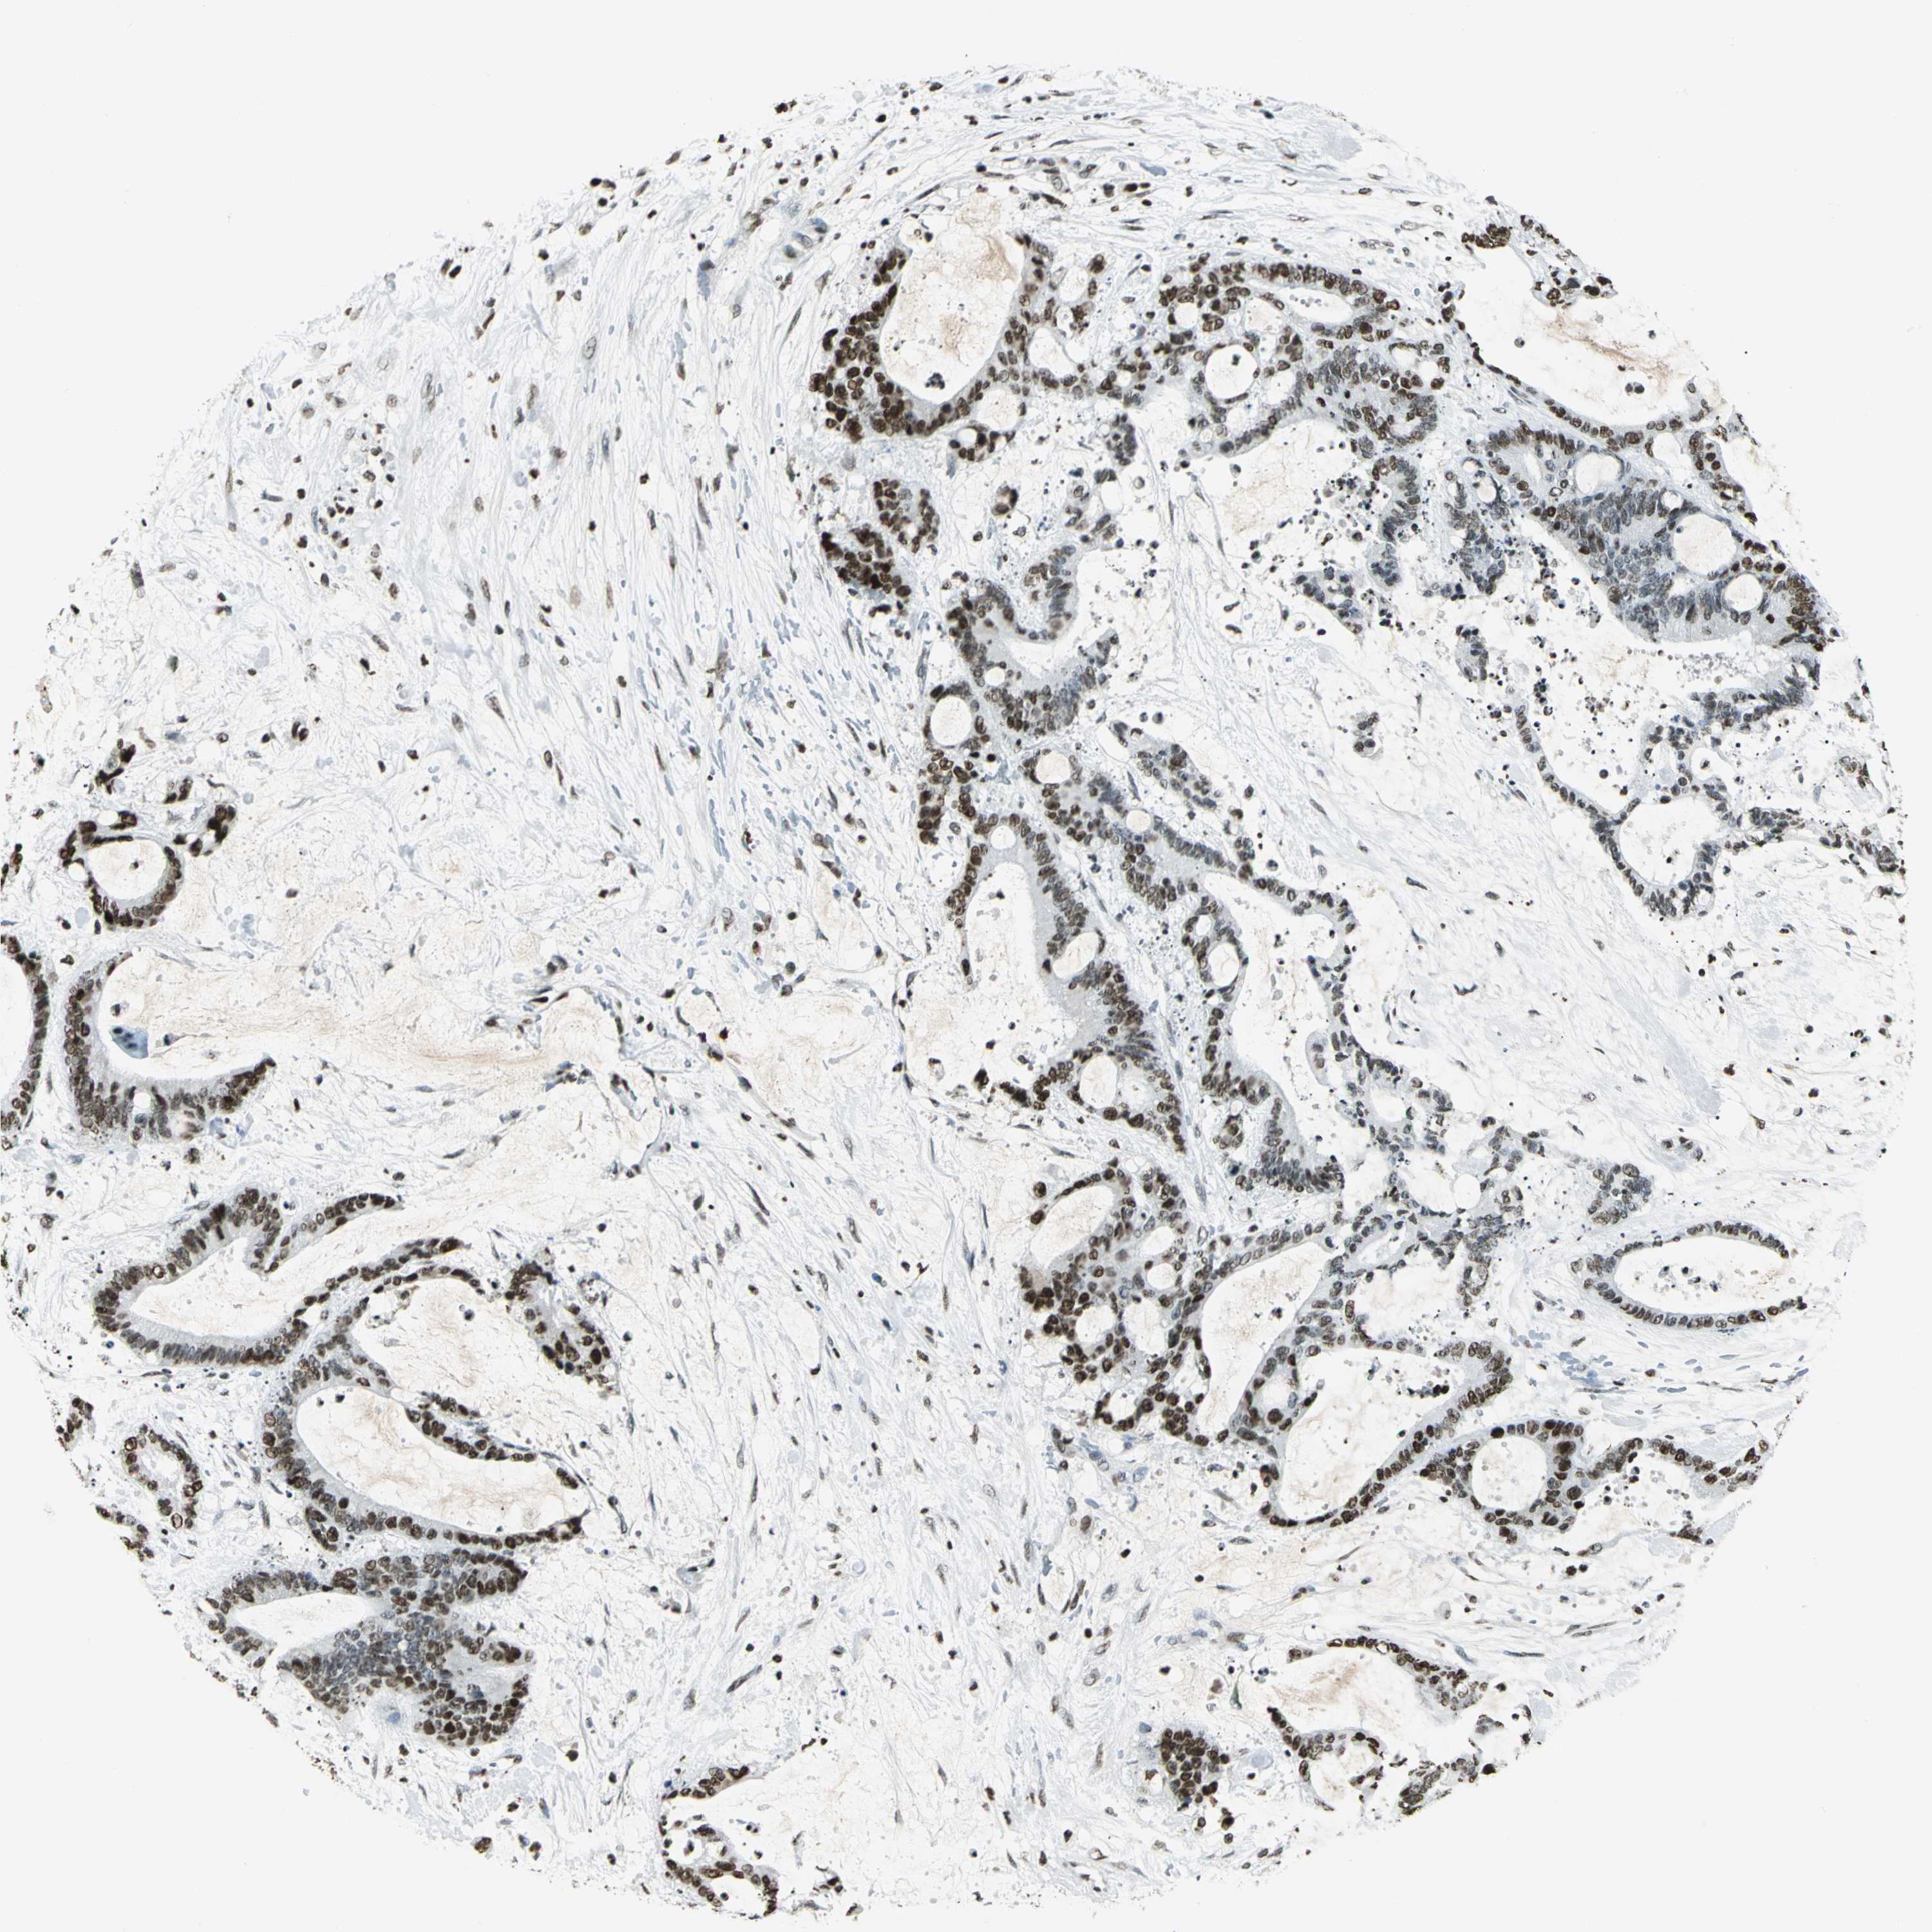

LIVER CANCER - Protein expressioni

A mouse-over function shows sample information and annotation data. Click on an image to view it in a full screen mode. Samples can be filtered based on level of antibody staining by selecting one or several of the following categories: high, medium, low and not detected. The assay and annotation is described here.

Antibody stainingi

Antibody staining in the annotated cell types in the current human tissue is reported as not detected, low, medium, or high, based on conventional immunohistochemistry profiling in selected tissues. This score is based on the combination of the staining intensity and fraction of stained cells.

Each image is clickable and will lead to virtual microscopy that enables deeper exploration of all samples and also displays staining intensity scores, fraction scores and subcellular localization as well as patient and tissue information for each sample.

Antibody CAB004497

Staining

High

Medium

Low

Not detected

Intensity

Strong

Moderate

Weak

Negative

Quantity

>75%

75%-25%

<25%

None

Location

Nuclear

Cytoplasmic/membranous

Cytoplasmic/membranous,nuclear

Cholangiocarcinoma

Carcinoma, Hepatocellular, NOS